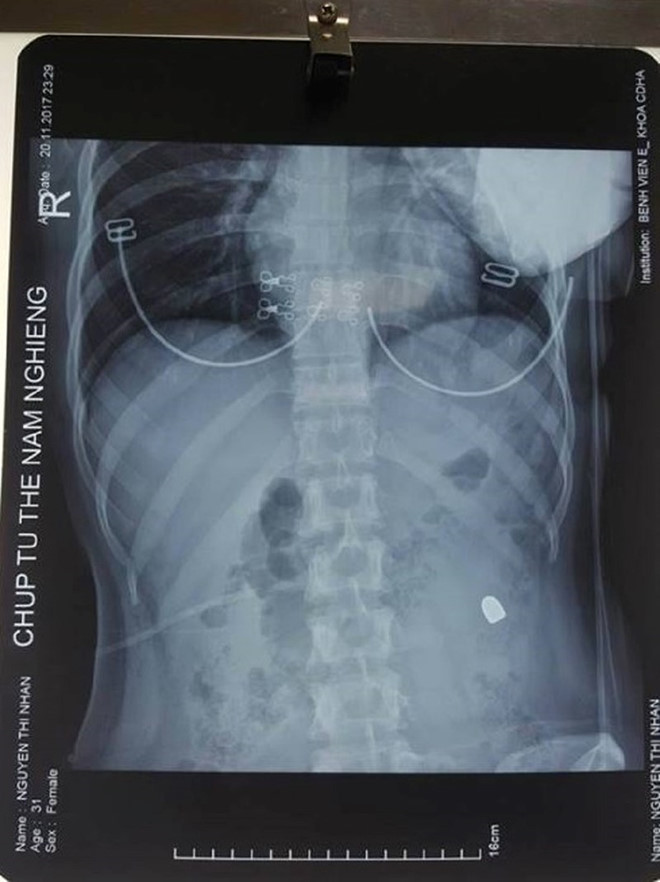

Ngày 21/11, theo thông tin từ bệnh viện E (Hà Nội), đơn vị này vừa mổ cấp cứu thành công cho một phụ nữ 31 tuổi, trú tại quận Bắc Từ Liêm, bị đạn bắn trúng ổ bụng.

Theo đó, khoảng 23h đêm 20/11, bệnh nhân này nhập viện trong tình trạng kích thích do hoảng sợ, đau khắp bụng và có vết thương ở vùng mạn sườn phải. Vết thương hướng từ phải sang trái, từ phía sau ra phía trước.

Kết quả chụp X-quang cho thấy một đầu đạn nằm tại mạn sườn trái của bệnh nhân, cô được đưa lên phòng mổ.

ThS.BS Trần Thượng Việt, người trực tiếp tiến hành ca mổ cấp cứu, cho biết bệnh nhân bị thủng đại tràng ngang 4 lỗ. Các bác sĩ quyết định cắt phần đại tràng ngang đó. Nếu bệnh nhân không được mổ cấp cứu kịp thời, nguy cơ tử vong là rất lớn do thủng đại tràng, sốc nhiễm khuẩn do viêm phúc mạc.

Ca mổ diễn ra căng thẳng nhưng thành công. Bệnh nhân không gặp biến chứng nào. Hiện, bệnh nhân đã ổn định và được chuyển xuống khoa ngoại tổng hợp để tiếp tục điều trị, dự kiến có thể được xuất viện từ 7 đến 10 ngày tới.